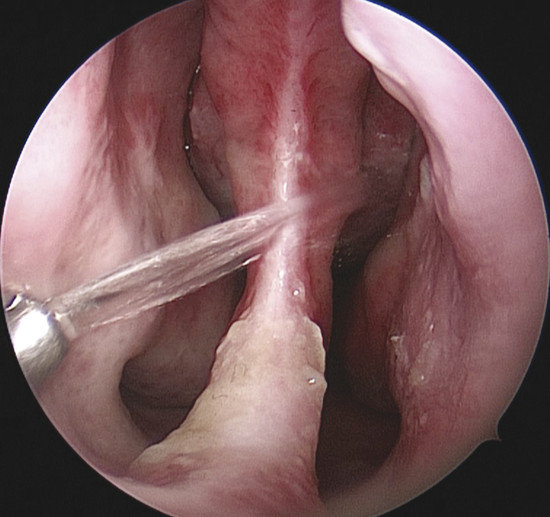

Nasal irrigation can also have different pressures for every requirement (Fig. 7‑1). Those with low-flow volume go out nebulized allowing a soft cleaning and humidification of the nasal cavity, preferring as a maintenance therapy when there is no much secretion and crusts. The medium-flow volume is recommended when wanting a thorough cleaning or there are some crusts, leaving the high-flow volume for severe crusting and secretions. For irrigation of the whole nasal cavity, compressible douching systems that have a minimum output pressure of 120 mbar, a good connection of the outlet to the nostril, and irrigation stream that is directed upward (45 degrees) are recommended (Fig. 7‑2). Moreover, the material should be transparent, easy to clean, and disinfect, and should not contain harmful elements. 18